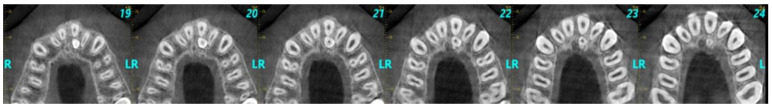

背景/目的:本回顾性研究的目的是调查非综合征希腊儿童和青少年上颌前区多生牙,以及它们与人口统计学特征和影像学表现的可能相关性。方法:研究样本包括224名年龄在18岁以下的儿童和青少年的锥形束计算机断层扫描(CBCT)。研究了上颌前区多生牙的位置、形态、与邻近解剖结构和邻近牙齿的关系以及可能的意义。结果:224例患者中有26例(11.6%)出现多牙。男性的患病率高于女性(分别为61.5%和38.5%)。在26名被诊断为多牙的儿童/青少年中,80.8%的儿童/青少年有一颗多牙,19.2%的儿童/青少年有两颗多牙。绝大多数多生牙阻生(92.3%),57.7%多生牙形态为锥形。正常体位占38.5%,倒置体位占26.9%,水平体位占19.2%,其他15.4%。84.6%的病例定位于腭部,50%的病例定位于中线。结论:希腊儿童和青少年多生牙的发生率为11.6%,多生牙多呈单牙、阻生、锥形、牙向正常。然而,由于抽样策略的局限性和本研究的有限推广性,这些结果应该谨慎解释。强调需要进一步研究,以加强对不同人口的更广泛适用性。这些发现有助于更全面地了解多生牙齿的患病率,有助于制定更准确和个性化的儿童和青少年牙科治疗计划。这将有助于避免病人的牙齿将来出现问题。

Background/Objectives: The aim of this retrospective study was to investigate the supernumerary teeth located in the anterior region of the maxilla of non-syndromic Greek children and adolescents, as well as their possible correlation with demographic characteristics and radiographic findings. Methods: The study sample comprised cone-beam computed tomography (CBCT) scans from 224 children and adolescents aged up to 18 years. The following parameters were studied: location of supernumerary teeth in the anterior maxillary area, their morphology, their relationship to adjacent anatomical structures and adjacent teeth, and potential implications. Results: Out of the 224 cases 26 (11.6%) presented supernumerary teeth. There was higher prevalence in males than females (61.5% versus 38.5%, respectively). Among the 26 participants diagnosed with supernumerary teeth, one supernumerary tooth was found in 80.8% of children/adolescents, while 19.2% had two supernumerary teeth. The vast majority of supernumerary teeth were impacted (92.3%), and their morphology in 57.7% of cases was conical. A total of 38.5% of cases had normal orientation, 26.9% inverted orientation, 19.2% horizontal orientation, and 15.4% other. The localization was palatal in 84.6%, and the area of localization for 50% of cases was the midline. Conclusions: The prevalence of supernumerary teeth in the studied sample of Greek children and adolescents was 11.6% and tended to appear as single, impacted, conical, and with normal orientation. However, these results should be interpreted with caution, due to the limitations in the sampling strategy and the restricted generalizability of this study. The need for further research to enhance broader applicability for different populations is highlighted. These findings are instrumental for a more comprehensive understanding of the prevalence of supernumerary teeth, contributing to more accurate and individualized dental treatment planning in children and adolescents. This will help to avoid future issues in the patient's dentition.